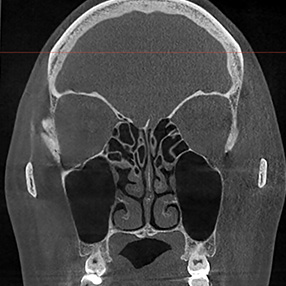

※ 축농증 수술 후 생길 수 있는 부작용으로는 출혈, 감염, 염증이 있을 수 있습니다.

본 사진은 의료기관에서 진료를 본 환자이고, 전후 사진 인물이 동일인이며,동일조건에서 촬영이 되었습니다.